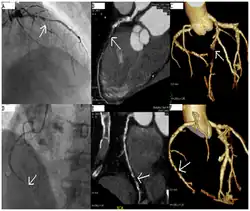

Coronary catheterization is one of the several cardiology diagnostic tests and procedures. Specifically, through the injection of a liquid radiocontrast agent and illumination with X-rays,[1] angiocardiography allows the recognition of occlusion, stenosis, restenosis, thrombosis or aneurysmal enlargement of the coronary artery lumens; heart chamber size; heart muscle contraction performance; and some aspects of heart valve function. Important internal heart and lung blood pressures, not measurable from outside the body, can be accurately measured during the test. The relevant problems that the test deals with most commonly occur as a result of advanced atherosclerosis – atheroma activity within the wall of the coronary arteries. Less frequently, valvular, heart muscle, or arrhythmia issues are the primary focus of the test.

If atheroma, or clots, are protruding into the lumen, producing narrowing, the narrowing may be seen instead as increased haziness within the X-ray shadow images of the blood/dye column within that portion of the artery; this is as compared to adjacent, presumed healthier, less stenotic areas.

CT angiography can act as a less invasive alternative to Catheter angiography. Instead of a catheter being inserted into a vein or artery, CT angiography involves only the injection of a CT-visible dye into the arm or hand via an IV line. CT angiography lowers the risk of arterial perforation and catheter site infection. It provides 3D images that can be studied on computer, and also allows measurement of heart ventricle size. Infarct area and arterial calcium can also be observed (however those require a somewhat higher radiation exposure). That said, one advantage retained by Catheter angiography is the ability of the physician to perform procedure such as balloon angioplasty or insertion of a stent to improve blood flow to the artery.[8]